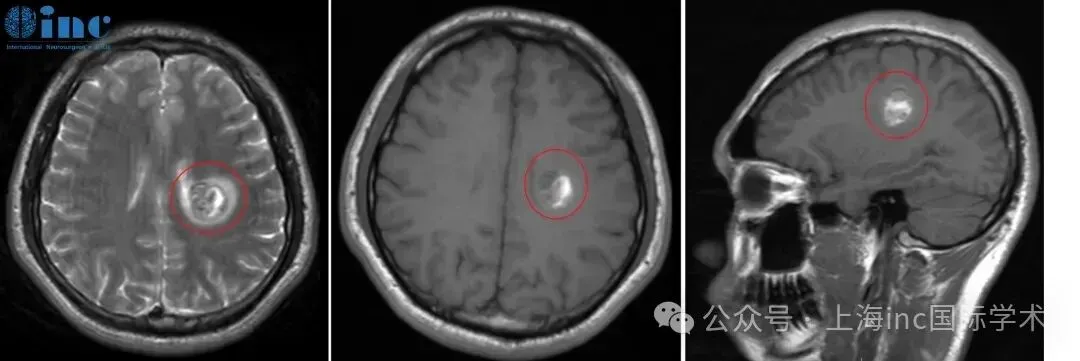

9岁的朋朋在半年来始终过的提心吊胆,她不得不提防着随时可能到来的癫痫,也必须忍受持续的头痛。然而,当父母带着她来到医院检查时,却被结果吓了一跳:脑中一个5cm大的海绵状血管瘤...